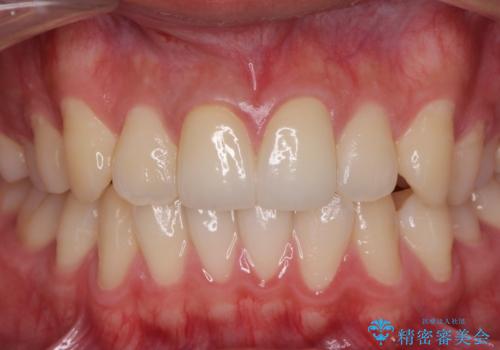

前歯を綺麗にしたい。

- 前歯を良くしたい(綺麗にしたい)との事で来院。

前歯のがたつきを治す治療プランとして

1 矯正を行い歯並びを良くする。(費用と時間がかかる)

2 セラミッククラウンで見た目を良くする(短時間で終わるが歯の向きを無理やり変えるために便宜的に歯の神経を抜く必要がある。健康な歯を削る)

のご提案をしたところ2のプランを選択されたのでセラミック治療を行いました。

見た目が良くなり大変満足して頂けました。